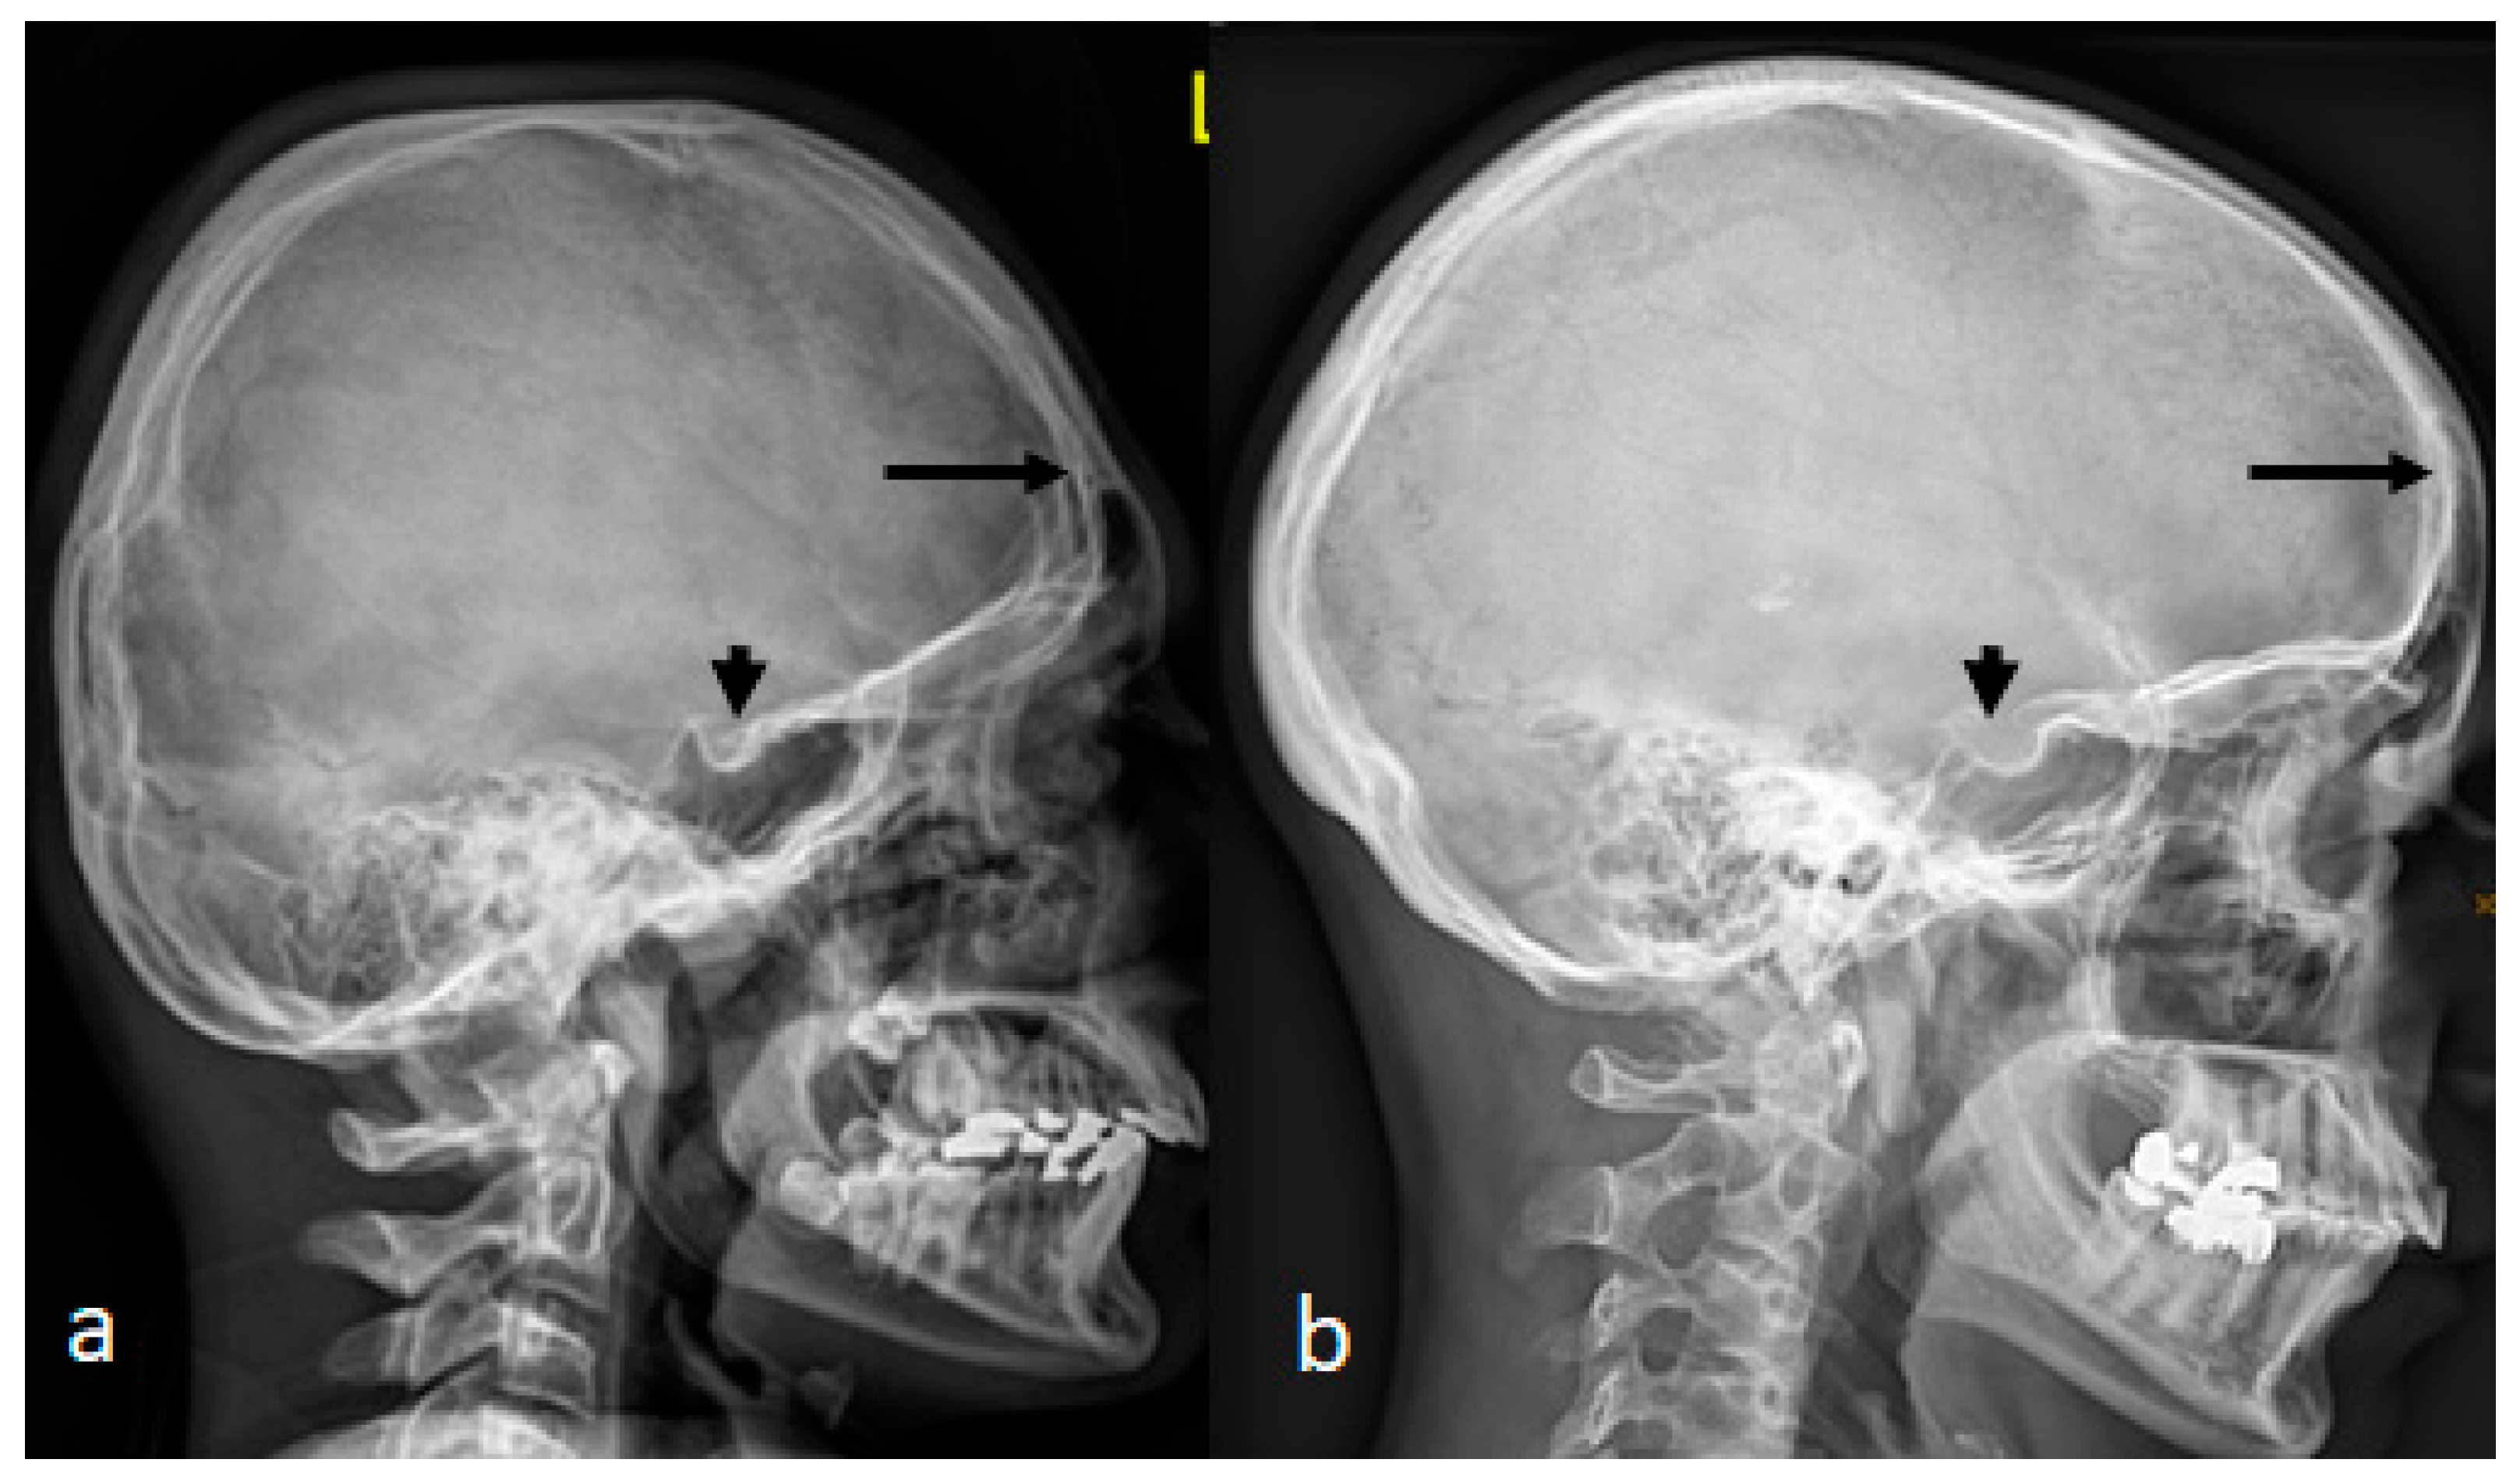

A 12-year-old boy with the diagnosis of West syndrome was referred to our department because of early-onset osteoarthritis. Interestingly, the child’s craniofacial contour resembles his 38-year-old mother.

A lateral skull radiograph of a 12-year-old boy with West syndrome showed premature sutural fusion, begetting an abnormal growth pattern, resulting in cranial deformity (brachycephaly). The nature of the deformity depends on which sutures are involved, the time of onset and the sequence in which individual sutures fuse. In this child, brachycephalic secondary to craniosynostosis occurred because of bilateral early ossification of the coronal sutures, leading to bi-coronal craniosynostosis. Note the ossified interclinoid ligament of the sella turcica (Figure 4a). A lateral skull radiograph of a 38-year-old mother with a history of poor schooling achievements showed a very similar cranial contour of brachycephaly and massive ossification of the clinoid ligament of the sella turcica. Maternal history revealed a history of multiple spontaneous miscarriages in the first trimester of more than five times.

Figure 4. (a) AP skull radiograph of a-12-year-old boy showed brachycephalic skull secondary to craniosynostosis occurred because of bilateral early ossification of the coronal sutures, leading to bi-coronal craniosynostosis. Note the ossified interclinoid ligament of the sella turcica. (b) A lateral skull radiograph of a 38-year-old mother with a history of poor schooling achievements showed a very similar cranial contour of brachycephaly and massive ossification of the clinoid ligament of the sella turcica.